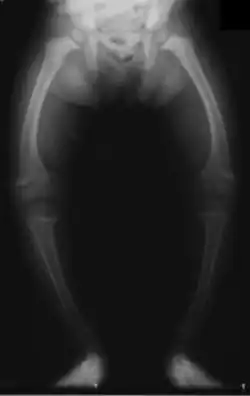

Primidone, along with phenytoin and phenobarbital, is one of the anticonvulsants most heavily associated with bone diseases such as osteoporosis, osteopenia (which can precede osteoporosis), osteomalacia, and fractures.[33][34][35] The populations usually said to be most at risk are institutionalized people, postmenopausal women, older men, people taking more than one anticonvulsant, and children, who are also at risk of rickets.[33] Bone demineralization is suggested to be most pronounced in young people (25–44 years of age),[34] and one 1987 study of institutionalized people found that the rate of osteomalacia in the ones taking anticonvulsants—one out of 19 individuals taking an anticonvulsant (vs. none among the 37 people taking none) —was similar to that expected in elderly people. The authors speculated that this was due to improvements in diet, sun exposure, and exercise in response to earlier findings, and/or that this was because it was sunnier in London than in the Northern European countries, which had earlier reported this effect.[35] In any case, the use of more than one anticonvulsant has been associated with an increased prevalence of bone disease in institutionalized epilepsy patients versus institutionalized people who did not have epilepsy. Likewise, postmenopausal women taking anticonvulsants have a greater risk of fracture than their drug-naive counterparts.[33]

Anticonvulsants affect the bones in many ways. They cause hypophosphatemia, hypocalcemia, low vitamin D levels, and increased parathyroid hormone. Anticonvulsants also contribute to the increased rate of fractures by causing somnolence, ataxia, and tremor, which would cause gait disturbance, further increasing the risk of fractures on top of the increase due to seizures and the restrictions on activity placed on epileptic people. Increased fracture rate has also been reported for carbamazepine, valproate, and clonazepam. The risk of fractures is higher for people taking enzyme-inducing anticonvulsants than for people taking enzyme-non-inducing anticonvulsants.[34] In addition to all of the above, primidone can cause arthralgia.[26]